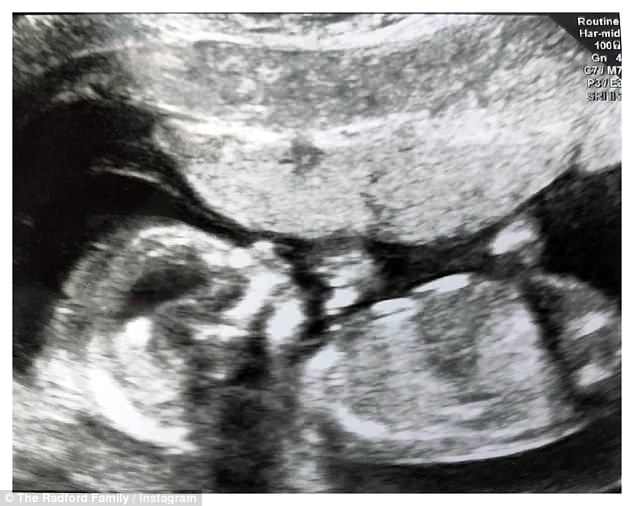

La nuova piccola, di cui la mamma e il papà hanno mostrato l’ecografia, andrà a fare compagnia ai fratelli e alle sorelle: Chris, Sophie, Chloe, Jack, Daniel, Luke, Millie, Katie, James, Ellie, Aimee, Josh, Max, Tillie, Oscar, Casper, Hallie, Phoebe, e Archie.

Nel filmato vediamo i genitori svelare il sesso del nascituro. “Moriamo dalla voglia di accoglierti nella nostra famiglia, preziosissimo piccolo”.

Un cannone che spara confetti rosa per aria conferma una femmina.